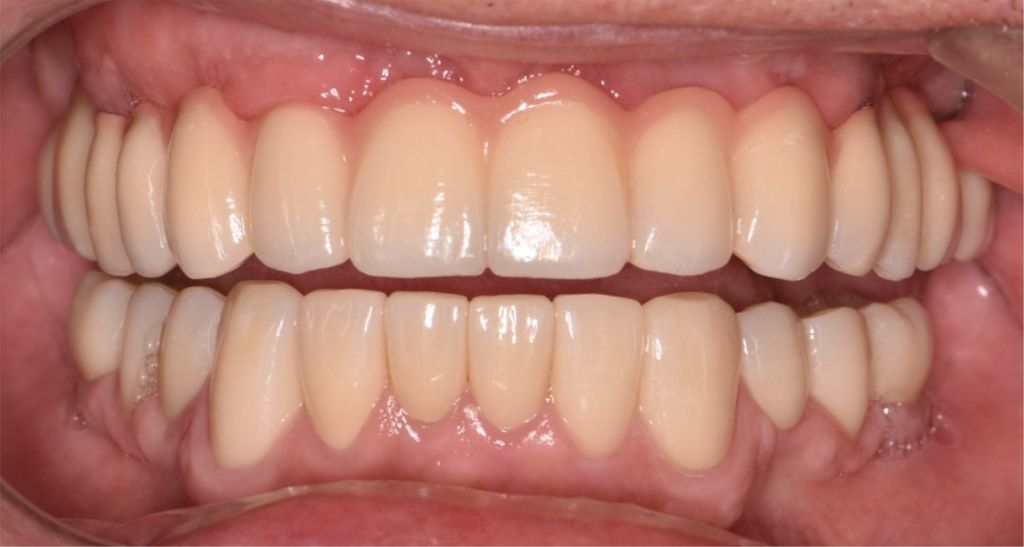

After

Before

Dental Bridge

Partial denture with precision attachments